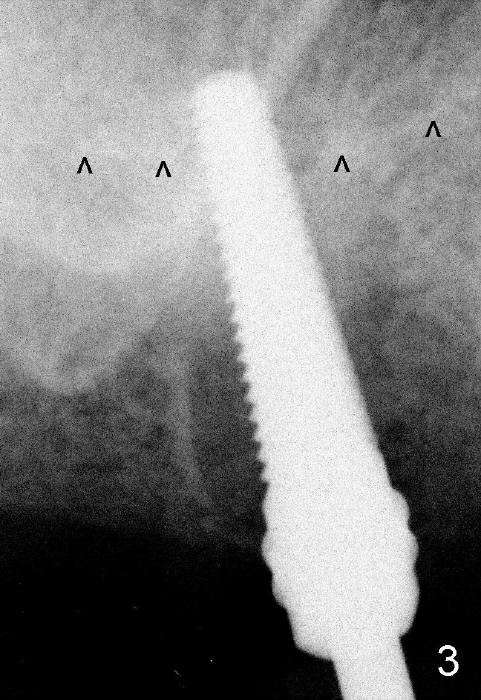

The upper right 1st molar fractures, the lingual portion mobile (Fig.1). There are deep pockets mesiolingually and distolingually. Fig.2 is preop PA, showing mesial bone resorption (*). The 84-year-old lady agrees extraction and immediate implant. Extraction is difficult due to not only root fracture but also hemorrhage. Following debridement of granulation tissue, the 3 sockets are packed with gauze for hemostasis. Even so, there is oozing from the bone. The septum can not be seen clearly. Its position is determined by an explorer. Osteotomes have to be used for osteotomy in the septum, followed by taps. The first intraop PA shows that 5x20 mm tap penetrates the sinus floor (Fig.3 ^). The osteotomy is further enlarged until 7x17 mm tap with stability (Fig.4). So far there has been no sign of sinus membrane perforation. Mixture of freeze dry mineralized bone and Osteogen is placed in the socket and pushed to the buccal and lingual walls as well as into sinus using a 4 mm flat end osteotome. A 7x17 mm implant is initially difficult to be inserted possibly due to blockage by bone graft. The osteotomy have to be recreated by a series of osteotomes and taps before placement of the 7x17 mm implant. It appears that the apical threads have been engaged into the sinus floor for primary stability (Fig.5). The insertion torque is 40 Ncm. According to our experience (1,2), this is not enough; finally the torque is increased to 60 Ncm by turning the implant more apically. The large implant obliterates the socket mesiodistally; the buccal and lingual gaps are filled with bone graft, followed by a collagen membrane (Fig.6 *) and suture. In order to protect the membrane, a short abutment is placed (A) and perio dressing (Fig.7*) is placed without occlusal interference. The abutment is removed 1 month postop, as the perio dressing has been dislodged. The patient returns for restoration 8 month postop. Bone regeneration occurs apparently in the coronal aspect of the implant (Fig.8), especially mesially (*, as compared to Fig.5). The gingiva-level implant is slightly subgingival mesially (Fig.9 M), probably due to high placement (compare to Fig.6). There is no bone resorption 6 months post crown (Fig.10 C) cementation.